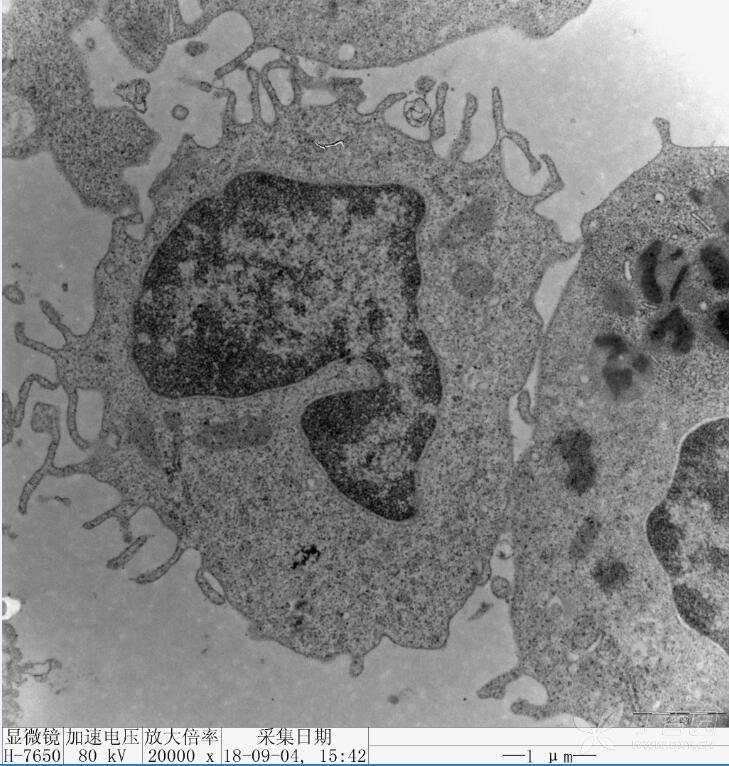

凋亡小体显微镜图

透射电镜观察凋亡

3 透射电子显微镜观察结果评判:凋亡细胞体积变小,细胞质浓缩.